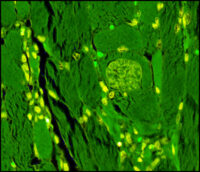

Sarcocystosis

Sarcocystis in Domestic Rabbits

What is Sarcocystis? Sarcocystis is a genus of single-celled parasites with a complex lifecycle involving […]